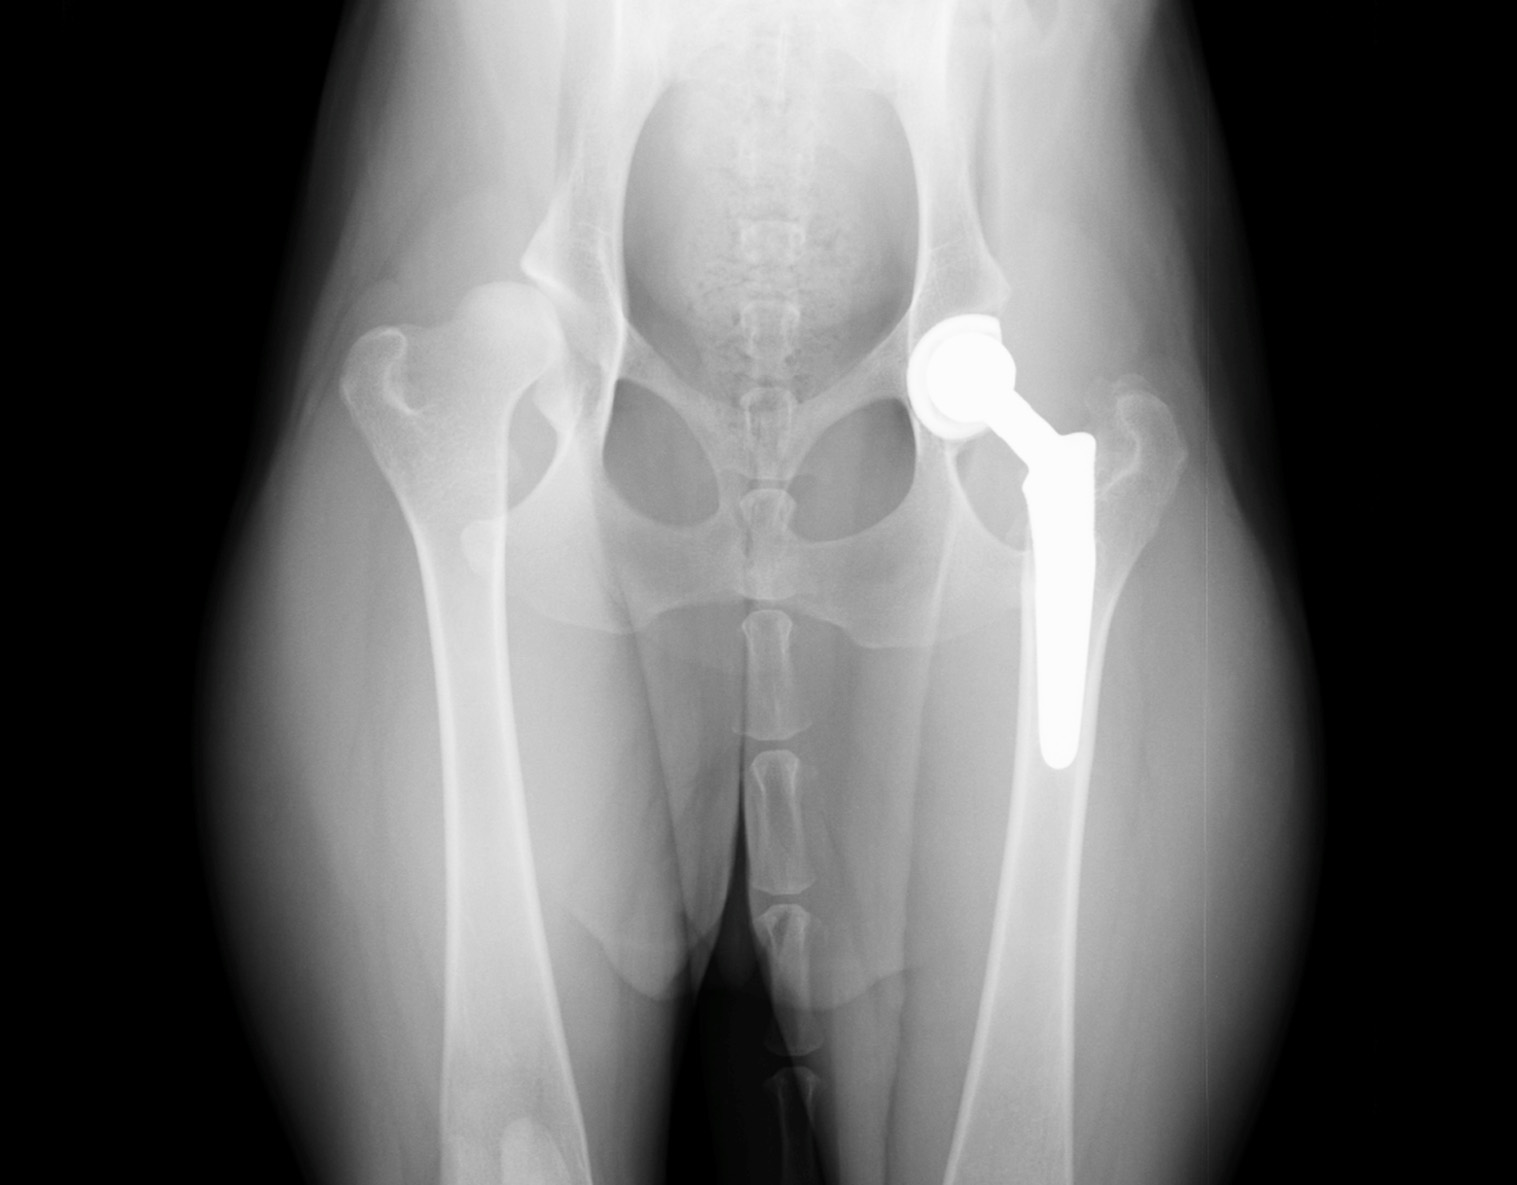

Product: BFX® Hip

“Anzu presented at one year old after being diagnosed with hip dysplasia. Her left hip underwent a total hip replacement on June 23, 2005, using the original BFX® cup and stem design. She recovered well and was able to walk without issue for 15 years! Throughout that time, she lead a happy life until she passed away from old age on July 3, 2020. Dr. Koreeda examined Anzu and found the artificial hip remained stable with no loosening or breakage. While the polyethylene showed slight wear, there were no clinical issues to report. Thanks to her THR, Anzu was able to walk without problems for 15 years following her procedure. Anzu’s family hopes her story will give other owners hope that their pets can be restored to full mobility and live long, happy lives!”